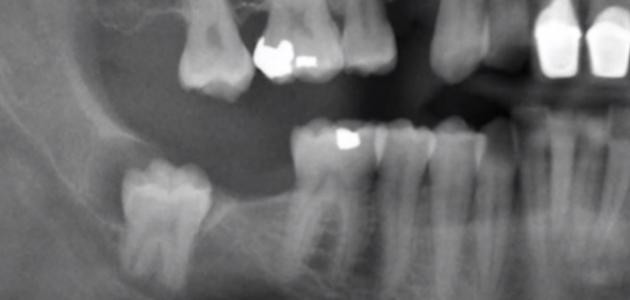

إن عدد الأضراس التي تظهر للإنسان الطبيعي هي أربعة ، اثنين بالفك السفلي واثنين بالفك العلوي وتظهر بأوقات مختلفة ضمن المرحلة العمرية الطبيعية التي تبدأ بها نمو الاضراس ولكن هناك بعض الحالات النادرة لنموها عند بعض الأشخاص وهي ظهورها كاملة بوقت قصير خلال سنة واحدة وبدون أي ألم وأعراض ومنهم من تتأخر لسن 35 تقريباً، يعتبر ألم الأضراس من الآلام الشديدة التي لا يستطيع الغنسان تحملها وتعود أسباب هذه الآلام لعم بزوغها بشكل صحيح بالفك حيث إنّه يطهر جزء منها أعلى اللثة والجزء الأكبر يبقى تحت عظام الفك وبهذه الحالة يحتاج لوقت طويل ليخرج ويبقى يسبب الوخز والألم من وقت لأخر.

يظهر ضرس العقل كباقي الـأضراس بالفك سليمة وصحية ولكن بسبب ضيق الفك أثناء ظهورها تجعلها عرضة للتسوس والتلف حيث لأنها يمكن أن تنمكو بشكل مائل يؤثر على السن المجاور مما يؤدي بهذه الحالة للتخلص من الضرسين بسبب الألم الشديد الذي تسببه هذه الحالة، غير أنّ جميع الأشخاص يلجؤون لخلع ضرس العقل بسبب تسوسه الكبير لعدم القدرة على ادخال الفرشاة لأخر الفك مما يؤدي لتجمع بقايا الطعام وهي البيئة المناسبة لنمو البكتيريا التي تسبب العديد من الاتهابات بالفم وتسوس الأضراس، يتم خلع أضراس العقل بشكل طبيعي عند طبيب الأسنان بحالة ظهور نسبة كبيرة منه أما بحالة عدم ظهوره وبقائه نامياً تحت اللثة فيتم إجراء جراحة لخلعه عن طريق عمل شق صغير من ثم خلع الضرس ويتم المعالجة بعد ذلك بتناول المسكنات وتناول المثلجات لوقف النزيف وبعض المضادات الحيوية.